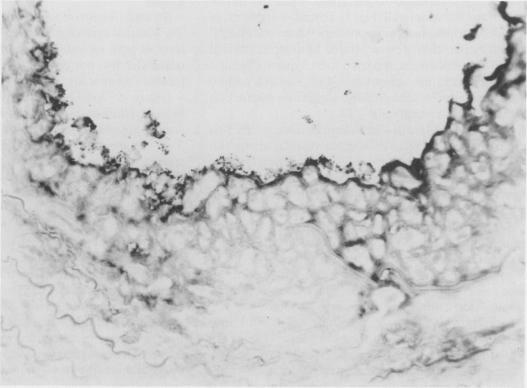

The vascular endothelium plays an important and complex role in vascular allograft rejection. Antigens expressed by the endothelium can act to promote and be the target of rejection reactions, which often lead to thrombosis and ischemic necrosis of the allograft. In this study, segments of femoral artery and femoral vein with or without endothelium were grafted between allogenic or autologous control rats. Immunocompetent Lewis (RT1(1] recipient rats were randomly selected for groups (N = 14 for each) receiving the following: ACI- (RT1a) allografts with intact endothelium, allografts with endothelium removed before operation, autografts with endothelium, and autografts with endothelium removed. Rejection was assessed by graft patency as well as morphologic and ultrastructural changes. At 5 days, the allografts with intact endothelium were totally occluded, whereas allografts without endothelium remained patent, as did autologous control grafts with or without endothelium. Two additional groups (N = 14 each) receiving the de-endothelialized allografts or autografts were examined at 120 days after operation, revealing that grafts in both groups were still patent and had been re-endothelialized. These findings indicate that physical removal of vascular endothelium may depress vessel allograft rejection without immunosuppressive therapy.

血管内皮在血管同种异体移植排斥反应中发挥着重要而复杂的作用。内皮表达的抗原可促进排斥反应并成为其靶标,这常常导致同种异体移植物的血栓形成和缺血性坏死。在本研究中,将有或无内皮的股动脉和股静脉段移植到同种异体或自体对照大鼠之间。随机选择具有免疫活性的Lewis(RT1(1]受体大鼠分为几组(每组N = 14),接受以下移植:具有完整内皮的ACI-(RT1a)同种异体移植物、术前去除内皮的同种异体移植物、具有内皮的自体移植物和去除内皮的自体移植物。通过移植物通畅情况以及形态学和超微结构变化评估排斥反应。在第5天时,具有完整内皮的同种异体移植物完全闭塞,而无内皮的同种异体移植物保持通畅,有或无内皮的自体对照移植物也是如此。另外两组(每组N = 14)接受去内皮同种异体移植物或自体移植物的大鼠在术后120天进行检查,结果显示两组移植物仍保持通畅且已重新内皮化。这些发现表明,在无免疫抑制治疗的情况下,物理去除血管内皮可能会抑制血管同种异体移植排斥反应。